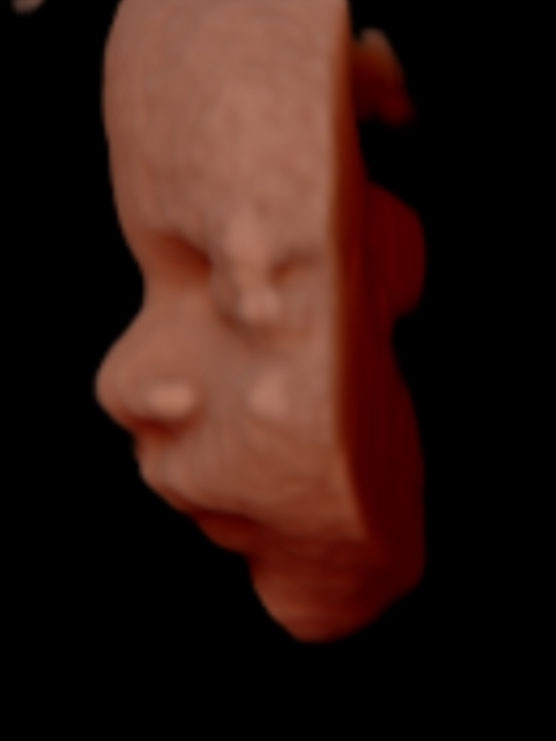

Dördüncü ayda bebek, biraz daha büyüyor, vücut hareketleri daha güçlü oluyor, parmaklarını hareket ettiriyor. Beşinci ayda yüz hareketleri, mimikleri başlıyor, tepkilere cevap veriyor. Altıncı ayda bebek, anne karnında iskelet gibi görüntüsünden daha dolgun hale geliyor. Bebeğin yüzünde dolgunlaşmalar başlıyor.

Yedinci aydan itibaren bebeklerde yavaş yavaş tüylenmeler görülüyor. Cildi normal bebek halini alıyor. Sekizinci ve dokuzuncu ayda bebek doğduğu pozisyona geliyor. Doğmuş bebeğin her türlü özelliğini taşıyor. Bu aylarda hızlı kilo alıyor. Dokuzuncu ayda doğumdan sonra gördüğünüz bebeği anne karnında birebir görüyorsunuz."

Gülen bebekler Kaçar, bebeklerin yüz mimiklerinin başladığı beşinci aydan itibaren anne karnındaki gülüşlerinin bile fotoğraflanabildiğini ifade ederek, "Hepsini yakalamak zor oluyor. Gülen bebekler, biraz da anne ve babaların şansı. Bir iki saniyelik bu anı yakalarsanız şanslısınız. Aileler, gülen bebeklerinin fotoğraflarını bazen albümün ilk sırasına yerleştiriyor" dedi.